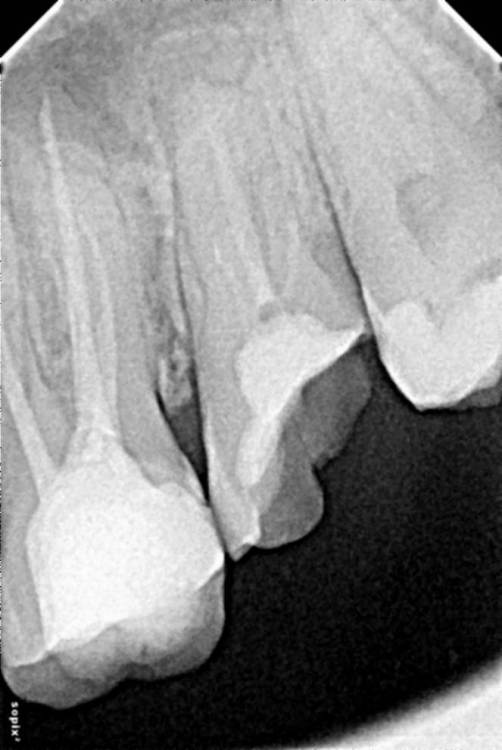

NinaAnn Опубликовано 14 апреля, 2023 Поделиться Опубликовано 14 апреля, 2023 Все требуют 3д снимки, что бы только сказать подлежит ли 7 восстановлению. Можно ли по ренгену хоть что то прояснить. Залечили 8й зуб 7 разрушен, 8 отвалилась стенка зуба. Делать 3 д перед диагнозом, потом если имплантация, снова 3д 1000 мкз тоже не просто снимок. 1й снимок месяц назад. 2й сегодня. Может просто снимок участка ренген что то поможет прояснитью Ссылка на комментарий

NinaAnn Опубликовано 14 апреля, 2023 Автор Поделиться Опубликовано 14 апреля, 2023 На восьмерке был дефект эмали и потом небольшая дырочка. я так понимаю что пломбу сделали огромную ставила цементную . Из простого цемента. Теперь и ее перелечивать видимо. Подскажите как теперь быть. Ссылка на комментарий

NinaAnn Опубликовано 15 апреля, 2023 Автор Поделиться Опубликовано 15 апреля, 2023 По ренгенам, говорят, о возможной кисте и воспалении. Импоантируют же в здоровую ткань. И 3 д снимок перед имплантацией после удаления и заживления. А это больше месяца. Не совсем понимаю что не потребуется ещё снимок. К тому же 6 тоже разрушен. А 8 единственный был живой но его залечили, именно залечили, громадная пломба. Может кто подскажет ещё тактику. У всех своя специализация, и на каждом этапе спецу свои данные. Ссылка на комментарий